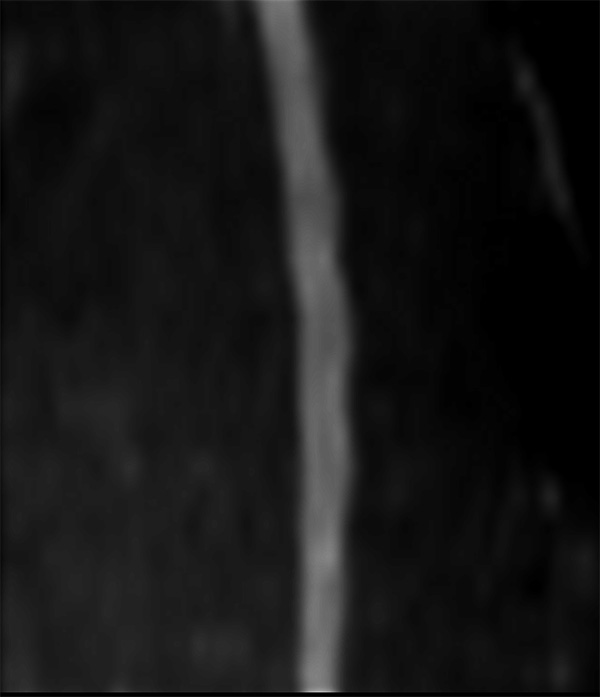

Comprehensive Cervical Spine imaging at 1.5T